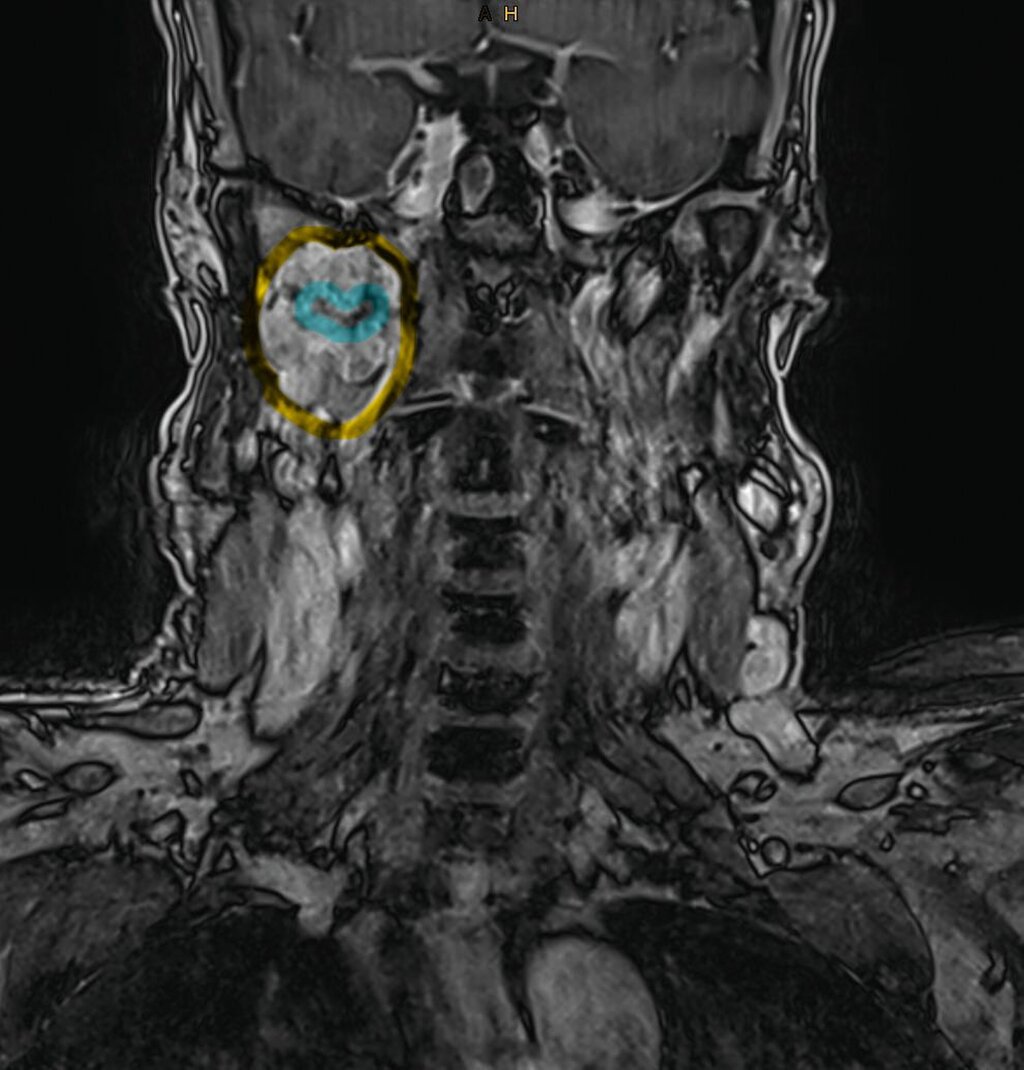

In der extern durchgeführten MRT der Halswirbelsäule vom 18. Dezember 2025 zeigte sich randständig eine angeschnittene Raumforderung im rechten Parapharyngeal- und Mastikatorraum, so dass eine gezielte weiterführende Bildgebung veranlasst wurde. Die kontrastmittelgestützte MRT vom 30. Dezember 2025 ergab eine inhomogene, gut abgrenzbare Raumforderung im rechten Parapharyngeal- und Mastikatorraum mit einer maximalen axialen Ausdehnung von 52 mm x 28 mm.

Die Läsion offenbarte ein zum Muskel isointenses T1-Signal sowie gemischt hyper- und hypointense Anteile in T2-gewichteten Sequenzen. Nach Kontrastmittelgabe imponierte eine kräftige, inhomogene Anreicherung; zentral bestanden nekrotische Areale. Eine Diffusionsrestriktion war inhomogen ausgeprägt.

Ein vaskulärer Ursprung konnte mittels dynamischer Sequenzen ausgeschlossen werden. Die Raumforderung wuchs verdrängend bis an den Musculus pterygoideus heran und hatte einen langstreckigen Kontakt von > 90° zur A. carotis interna. Zusätzlich bestand eine schlitzförmige Kompression der V. jugularis interna sowie eine fokale Teilthrombosierung der V. facialis communis. Pathologisch vergrößerte Lymphknoten waren nicht nachweisbar.

Zur besseren räumlichen Einschätzung wurde das MRT-Datenset mittels der Open-Source-Software 3D Slicer segmentiert [Fedorov et al., 2012]. Mithilfe der Funktion „Grow from seeds“ erfolgte eine separate Segmentierung des Unterkiefers und der Raumforderung, ergänzt durch manuelle Korrekturen.

Metallartefakte durch zahnärztliche Restaurationen im rechten Unterkiefer wurden berücksichtigt. Die dreidimensionale Rekonstruktion verdeutlichte die enge Beziehung des Tumors zur A. carotis interna und unterstützte die Indikationsstellung für einen erweiterten operativen Zugang.